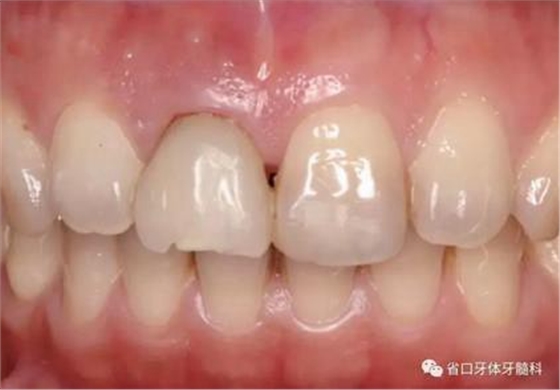

1.?病例簡介 43歲女性患者,主拆:右上前牙松動不適數(shù)日要求修復(fù)。現(xiàn)病史:患者數(shù)年前右上前牙因“齲壞”于外院行根管治療(具體不詳),數(shù)日前牙冠松動不適,現(xiàn)覺影響咀嚼及美觀,遂來我院要求進(jìn)一步診治。否認(rèn)高血壓、心臟病等重大疾病,否認(rèn)結(jié)核、肝炎等傳染病史,否認(rèn)手 術(shù)、輸血史等,未發(fā)現(xiàn)藥物過敏。無吸煙習(xí)慣。臨床檢查:口外觀顏面基 本對稱,皮膚無紅腫破潰,顳下頜關(guān)節(jié)區(qū)無彈響、雜音、壓痛,開口度約 37mm,開口型“↓”,頜下、刻下和頸部未及腫大淋巴結(jié)。中位笑線??趦?nèi)檢查,口腔衛(wèi)生可,色素(+),BOP(-),PD=2mm,上頜右側(cè)中切 牙冠部變色,冠根折斷至齦下3mm,叩不適,松動Ⅱ°~Ⅲ°。牙齦稍紅, 齦緣水平及齦乳頭高度可,屬于中厚齦生物型,附著齦寬度約5mm,唇系帶附著可。上頜右側(cè)中切牙缺牙間隙與對側(cè)同名牙一致,約>7mm,修復(fù)空 間良好。與對頜牙覆合覆蓋正常。MCT檢查示上頜右側(cè)中切牙冠根折斷至骨 下,根管內(nèi)見充填物,根充不全,根尖見陰影,大小約3mm×3mm。牙槽窩根方可用骨量可,唇側(cè)骨壁完整,冠方骨壁厚度約1mm。

圖1 術(shù)前口內(nèi)照

圖2 術(shù)前口內(nèi)照

圖3 術(shù)前口內(nèi)照